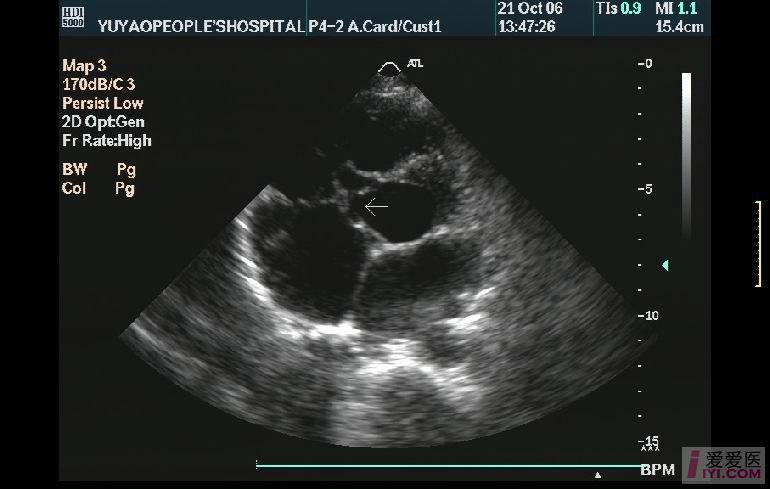

主动脉右冠窦瘤破裂破入右房